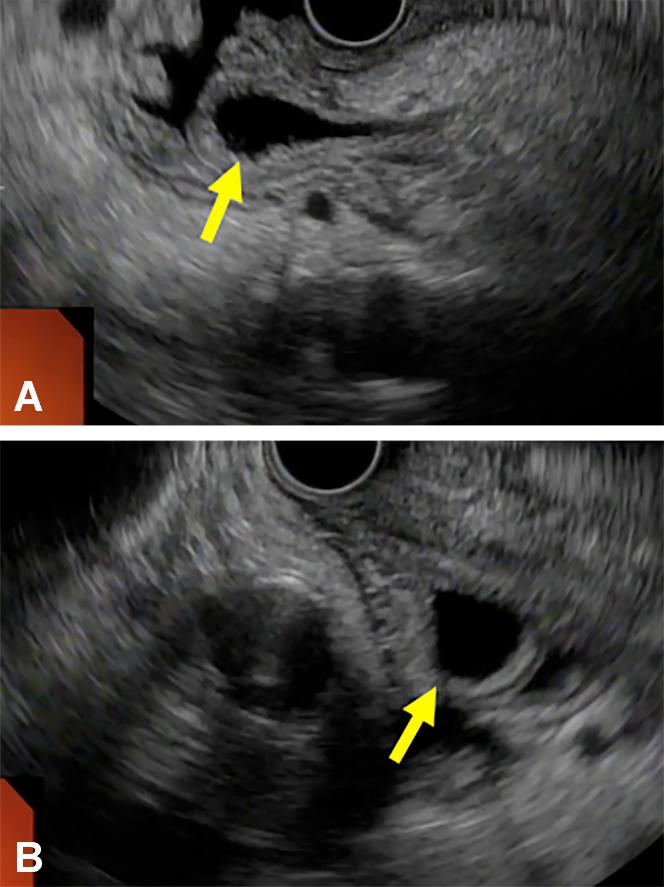

Abou Saleh Mohannad, Vozzo Catherine, Chahal Prabhleen

Department of Gastroenterology and Hepatology, Cleveland Clinic Foundation, Cleveland, Ohio.

VideoGIE. 2020 Dec 10;6(2):98-100. doi: 10.1016/j.vgie.2020.10.015. eCollection 2021 Feb.